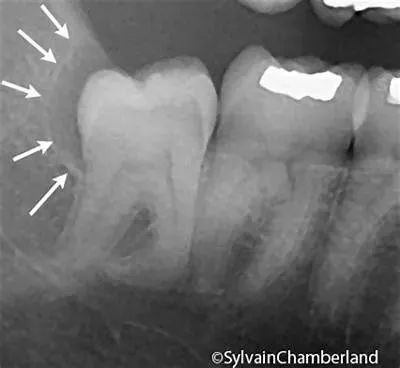

有条件的就选择微创拔牙,传统拔牙是以“锤、劈、敲”等方式进行,近几年随着口腔外科微创理念的不断发展,拔牙技术和器械的不断革新,微创拔牙应运而生,大大减轻患者拔牙时的痛苦。

由于微创拔牙器械的薄而锋利,可以快速而准确地切断牙周膜,保护牙槽骨的完整性,手术损伤小,术后疼痛轻,创口愈合也比传统拔牙后恢复得快。

微创拔牙尤其适合对付各种智齿↓